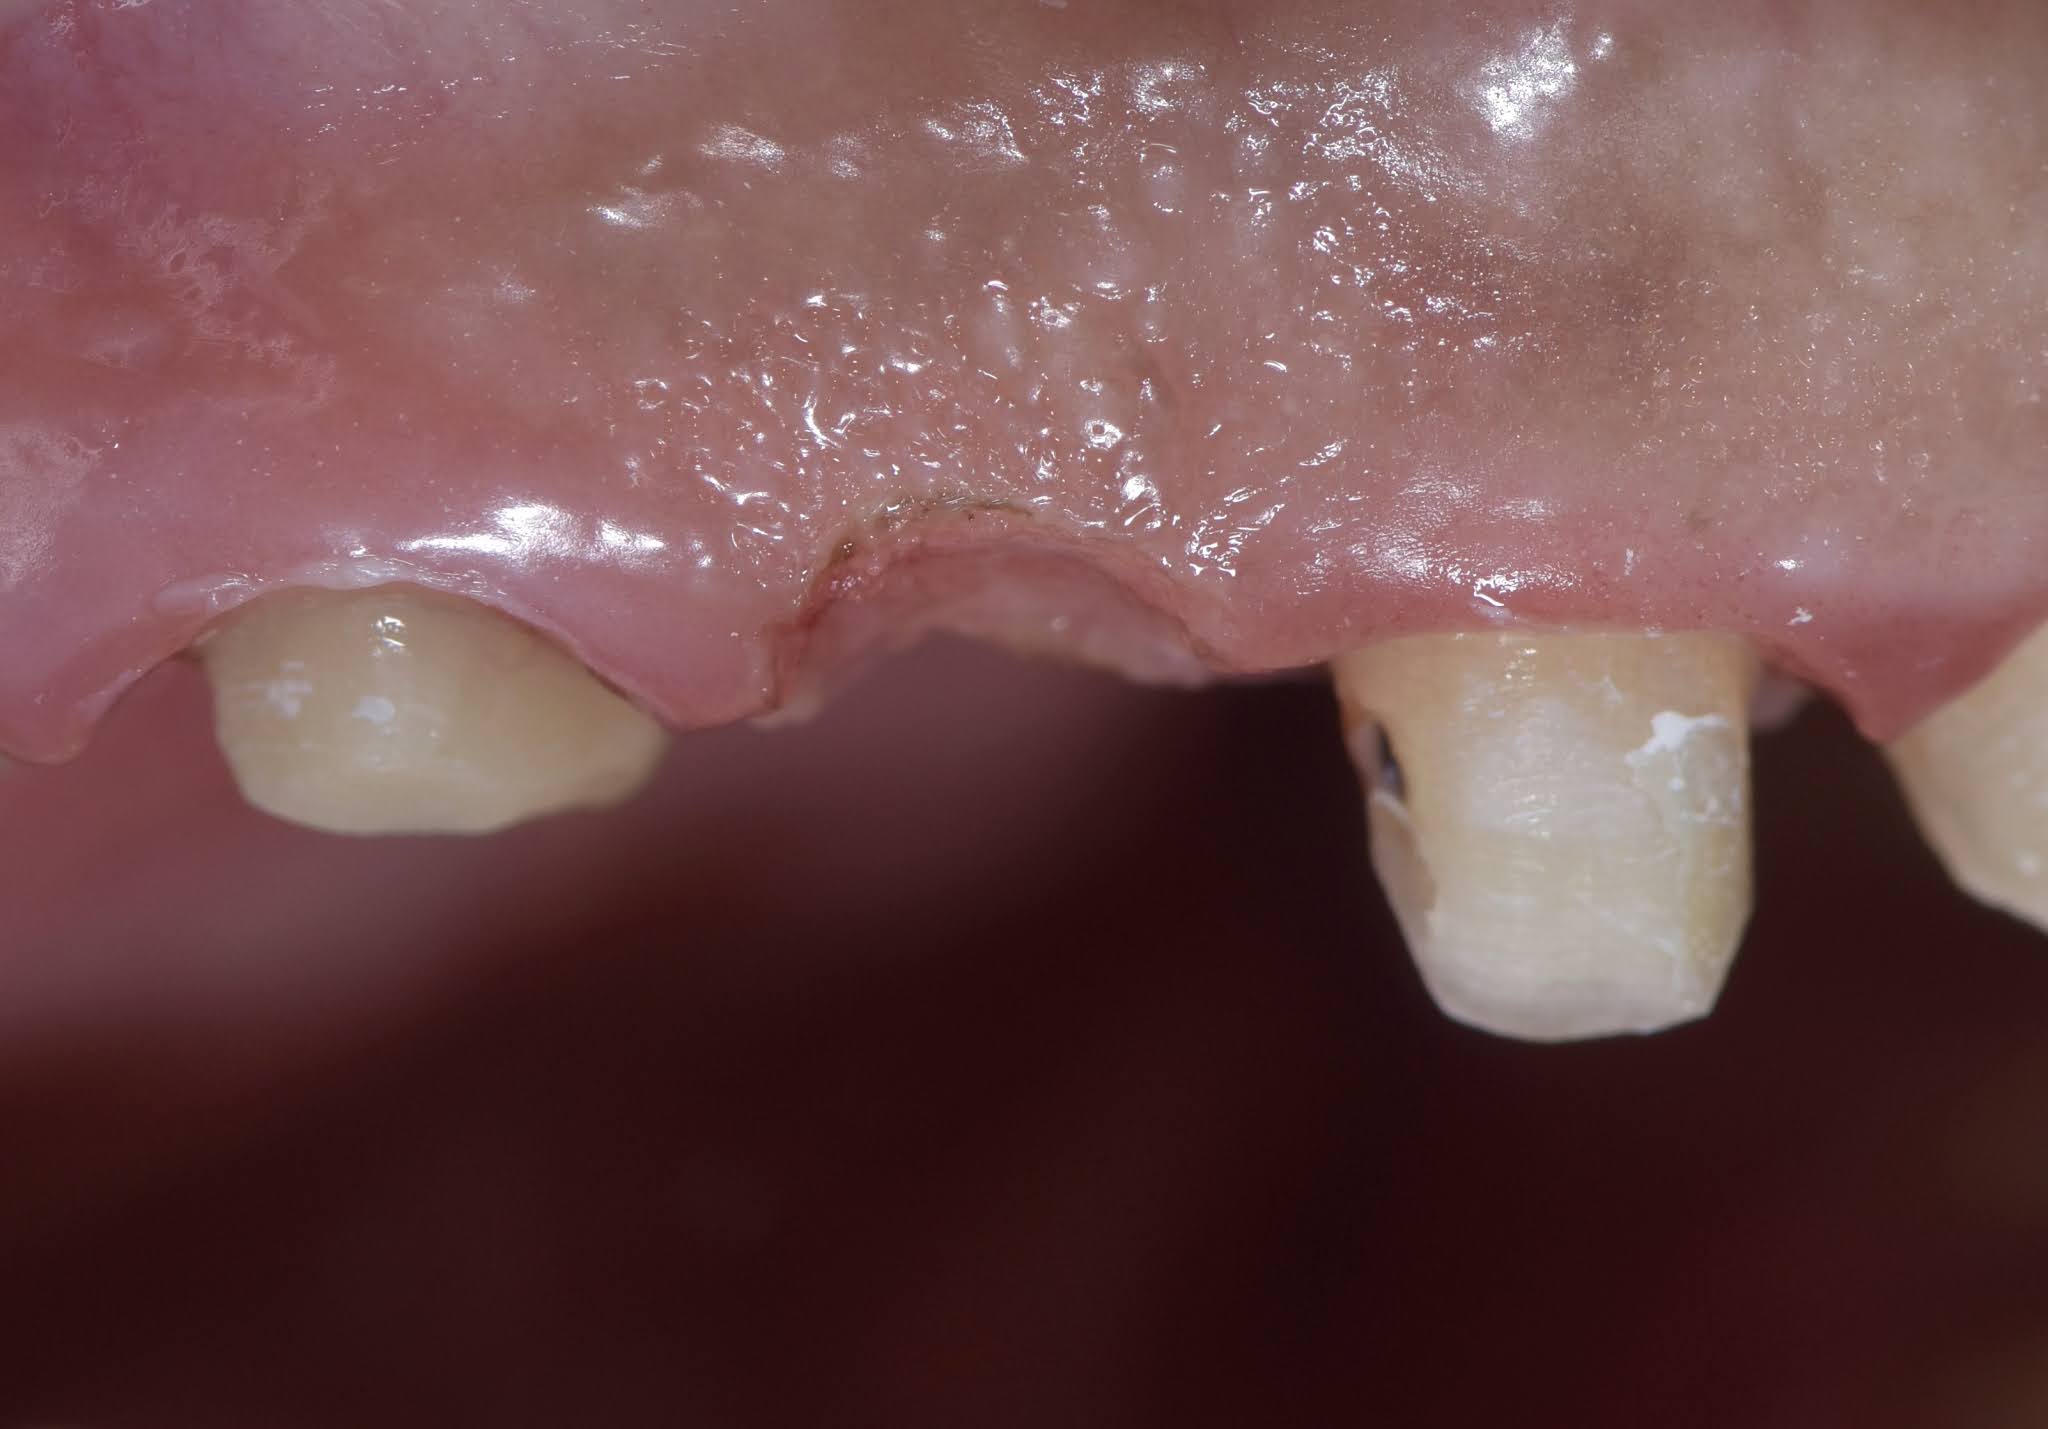

From www.todaysrdh.com

A Look at Pontic to Natural Tooth Bridges Today's RDH Dental Code For Bridge Pontic d6245 is the ada cdt dental code for a pontic in a fixed bridge. cdt codes to report dental bridges include d6245, d6740, d6240, d6241, d6242, d6750, and d6751. Used for a bridge where the pontic is entirely made from porcelain or ceramic, providing. The above codes are to be used to report the missing tooth (pontic) which. Dental Code For Bridge Pontic.